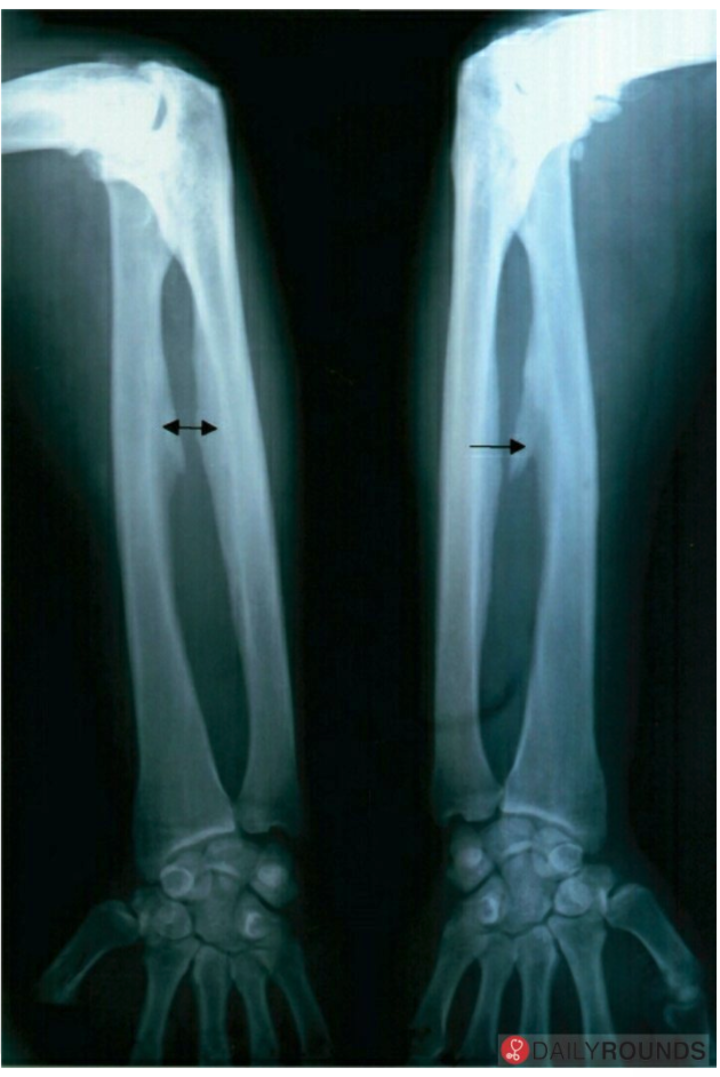

Interosseous membrane ossification is characteristic of _____.